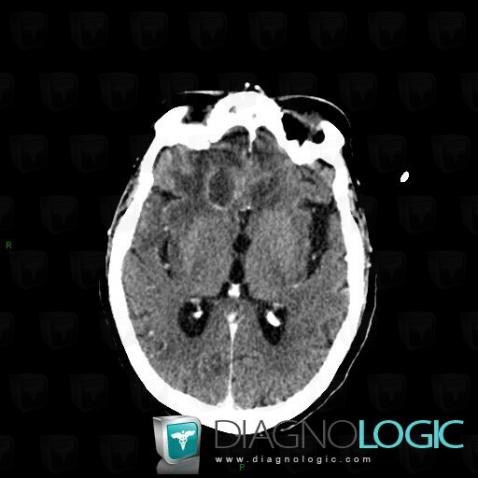

Abscess, Cerebral hemispheres, CT

Here is the specific information in the key image above:

- Diagnosis Abscess, Location(s) Cerebral hemispheres, with gamuts Intracerebral mass, Intracerebral lesion with ring enhancement, Multifocal intracranial lesions, Intracerebral lesion with moderate enhancement